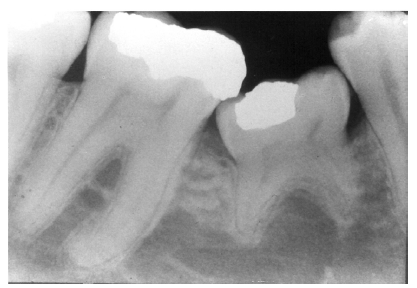

Figure 3 - Dentin Caries

Figure 3

Dentin caries extends into the tooth dentin and can be recognized by noting the focal loss of dentinal radiopacity. Most commonly, this darkened dentin is located beneath carious enamel and, typically, the lateral dimension of the dentinal involvement exceeds that of the associated enamel caries (Figure 3). Dentin caries may be discerned interproximally, on the occlusal surface, buccally/lingually, or on root surfaces.

Incipient occlusal dentin caries may be difficult to identify on radiographic images and root caries must be carefully distinguished from cervical burnout, as we will discuss later.